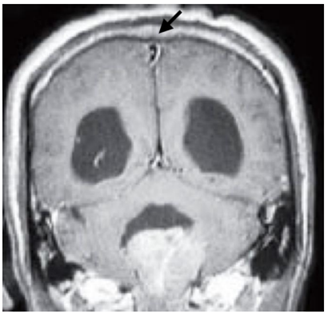

A seta na ressonância magnética acima está indicando a seguinte estrutura: